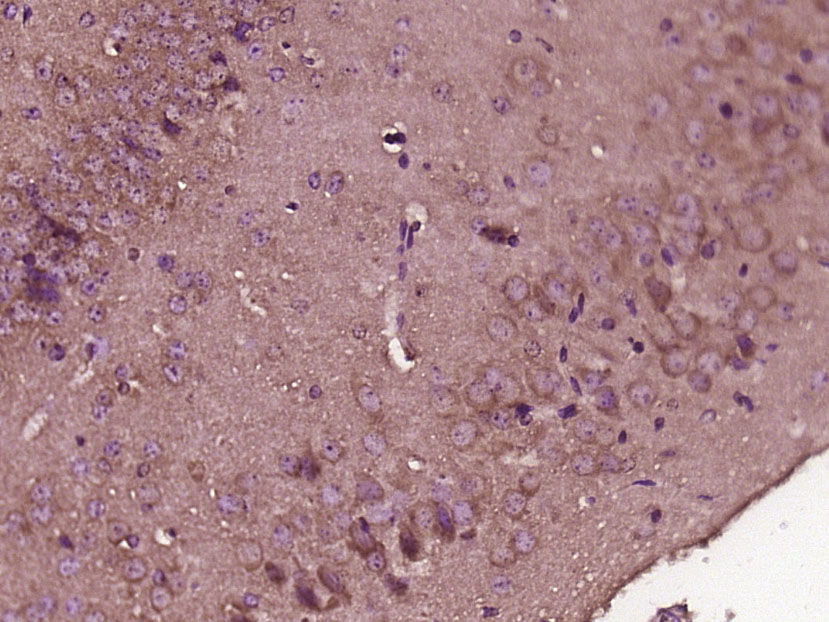

Paraformaldehyde-fixed, paraffin embedded (Mouse brain); Antigen retrieval by boiling in sodium citrate buffer (pH6.0) for 15min; Block endogenous peroxidase by 3% hydrogen peroxide for 20 minutes; Blocking buffer (normal goat serum) at 37°C for 30min; Antibody incubation with (LIAS) Polyclonal Antibody, Unconjugated (bs-18247R) at 1:500 overnight at 4°C, followed by a conjugated secondary (sp-0023) for 20 minutes and DAB staining.